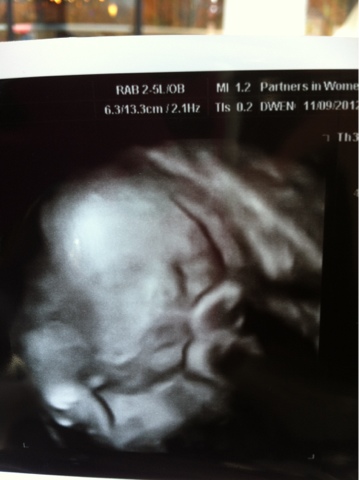

So--- I went into the doctor today for an ultrasound @ 32 weeks. The ultrasound tech took all of Lucie's measurements. Then she took them again. I was watching as each measurement popped a different gestational value on the screen from 31-36 weeks. Her head is like 36 weeks size. Her femur length is full term already I'm pretty sure. At this gestational age she's supposed to weigh about 3 1/2 lbs. they estimated her at 4 lbs 14 oz today. She's almost a 5 lb baby and I have 8 or 9 weeks to go?! Wait... What was that about the baby gaining a half a pound or more per week for the rest of the third trimester? Yikes! I'm totally freaked out that this girl is going to be HUGE. I am legitimately worried about a double digit weight at this point. They are going to do an LGA (large gestational age) ultrasound at BHE in a few weeks to see if their measurements come up the same...

The good news is she is otherwise healthy. Her heart rate is 153 still and she's really active. I got a picture of her but her face looks totally smushed up.